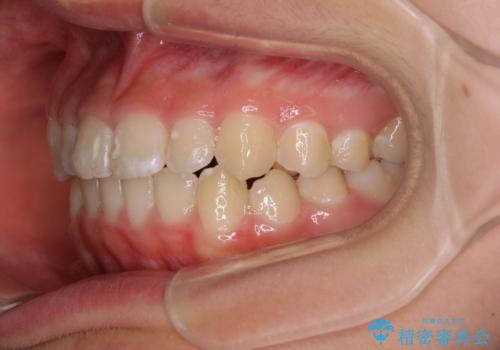

遠方から新幹線で通院 急速拡大装置とインビザラインによる矯正治療

- 小児矯正の頃から診察を行っている患者様です。

上顎骨の幅が下顎骨よりも小さいので、拡大装置により骨幅を広げて上下関係を改善し、その後インビザラインにて歯並びを整えることとしました。

上下の骨幅を改善したことで、スムーズに歯列矯正を行うことができました。

インビザライン治療開始直後に遠方に引っ越しをされたため、通院間隔が長くなり、治療期間が長くなりましたが、しっかりと治療を行うことができました。